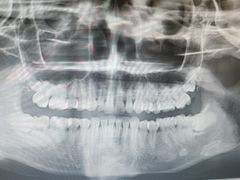

• -上海市徐汇区口腔医院

排骨糯米 | 25-07-26

报错